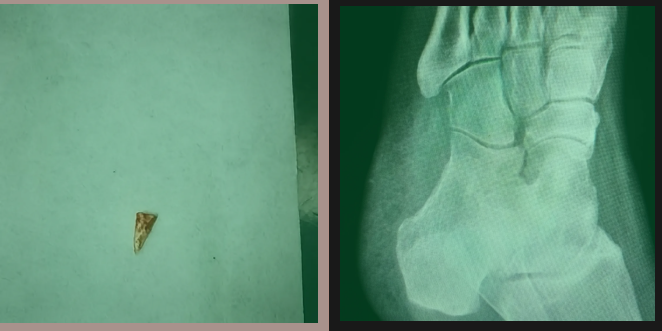

钱医生与赵女士进行了详细的沟通,考虑到存在异物的可能性,建议先对受伤部位进行X线检查。由于无法明确异物的性质,X线检查可能无法清晰显示异物的存在,但对判断病情仍有一定的帮助。不出所料,检查结果出来后,乍一看似乎并没有发现异常。然而,钱医生对着电脑仔细观察了许久,看出了些端倪:在赵女士的足底,有一个模糊的三角形影子。钱医生深知这个细节的重要性,于是立即请影像学专家、副院长戴燕飞和吴明峰主任进行会诊。

为了进一步明确情况,专家建议先通过清创探查,根据探查结果再考虑是否需要进一步扩创治疗。消毒麻醉后,钱医生在疼痛部位的那个黑点处,通过针尖小心探查,感觉到一个质地坚硬的物体抵着针尖。凭借多年的临床经验,钱医生沿着异物周围组织间隙小心地划出一个2毫米的切口,然后小心翼翼地分离异物周围的组织。随着操作的进行,真相终于大白:原来异物是一根3毫米长的灰白色三角形骨头,和X线上的影子完全一致。异物被完整地取出,困扰了赵女士一个多月的病痛根源终于彻底被拔除了。赵女士的脸上露出了久违的笑容。